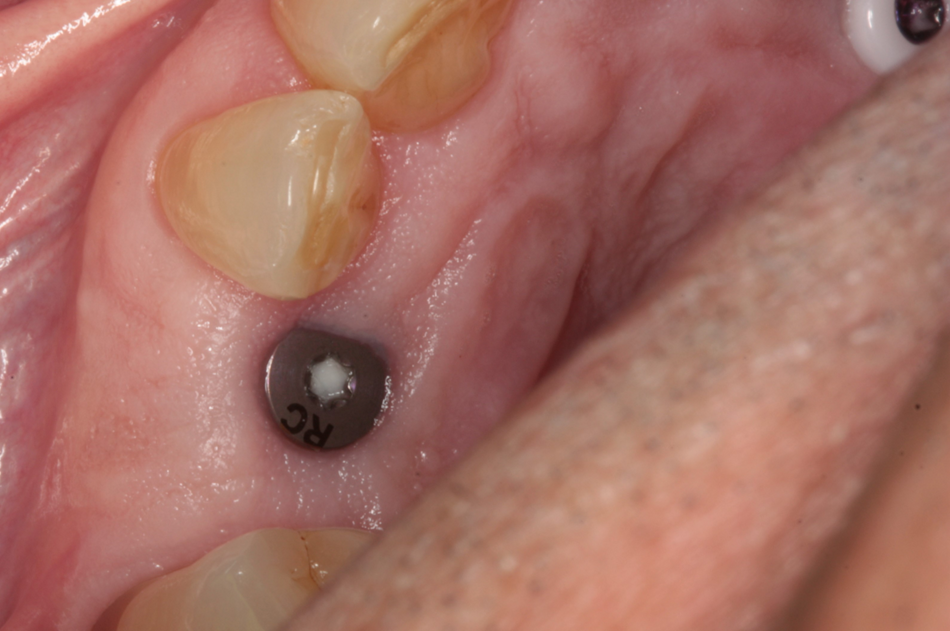

At the time of the second stage (Figs. 8- 10), we screwed a classic titanium healing abutment into implant 13 and a ceramic healing abutment on implant 23 (Figs. 11-14). The Ceramic Healing Abutments are composed of an external Zirconia body, while the internal part consists of a titanium screw that allows the tighten into the implant. We therefore made sure to put a chlorhexidine gel on the titanium part to avoid bacterial contamination.